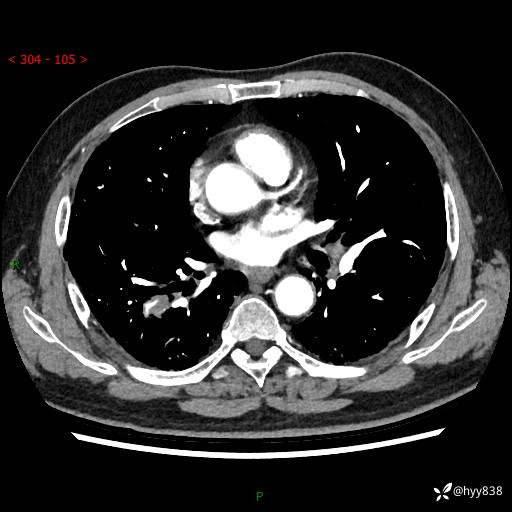

71岁/男,咳嗽伴气促半月。一年前肺手术史,又见两个结节,穿刺结果意外---结果公布~

【现病史】:患者半月前无明显诱因出现咳嗽、咳痰,为白色粘痰,无明显加重与缓解因素,伴气促,无发热,无大量脓痰,无胸痛、咯血,无哮鸣音,到我院就诊,胸部CT示右肺结节增大,并口服药物治疗无明显好转,具体用药不详,为求进一步治疗随来我院,经门诊以“孤立性肺结节”收入我科。 病程中患者精神、饮食可,睡眠不佳,大小便正常,体力下降,体重未见明显下降。

[既往史]:2022-06于当地第一人民医院确诊慢阻肺,现规律使用杰润(1次/日);2023-04-06于当地市第一人民医院行胸腔镜右肺上叶楔形切除术+右肺上叶切除术+淋巴结清扫术+胸膜黏连松解术,确诊为右肺鳞癌 pT2aN0M0 Ib期

【检查】:胸部CT平扫+增强